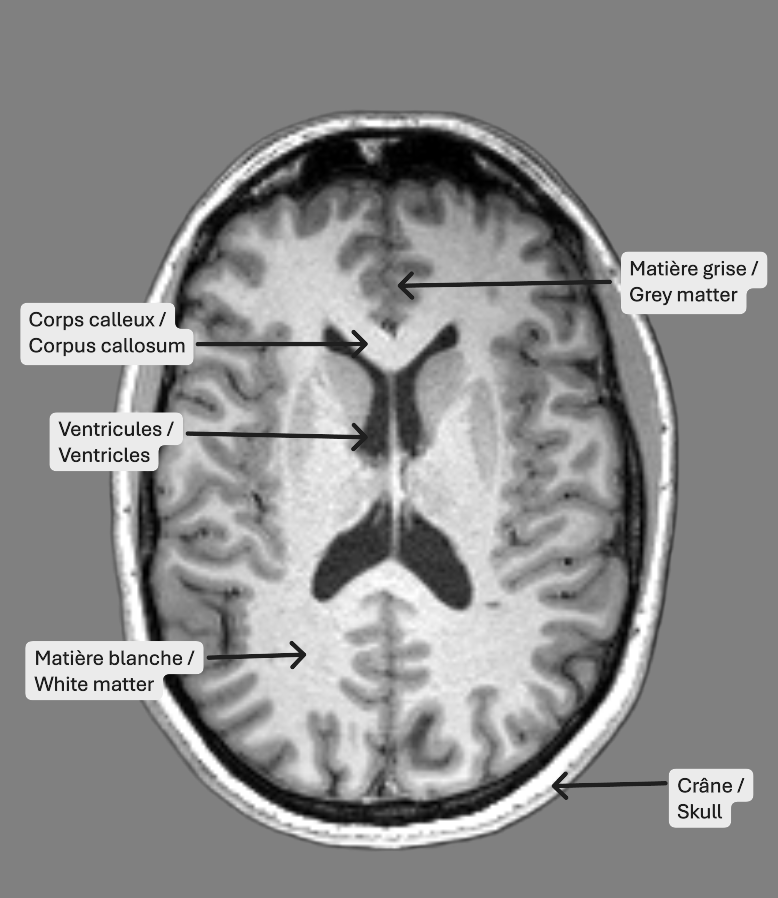

Identification des structures

Les tissus les plus facilement identifiables sur les images IRM pondérées en T1 sont les ventricules, la matière blanche et la matière grise. Les ventricules, en noir, sont des cavités contenant le liquide cérébrospinal, qui circule également dans les méninges. La matière blanche est constituée des axones des neurones et des connexions entre ceux-ci, et est représentée en gris pâle. En gris foncé, on retrouve la matière grise, qui comprend les corps cellulaires des neurones.

Pilot MRI Data from the Douglas Research Centre